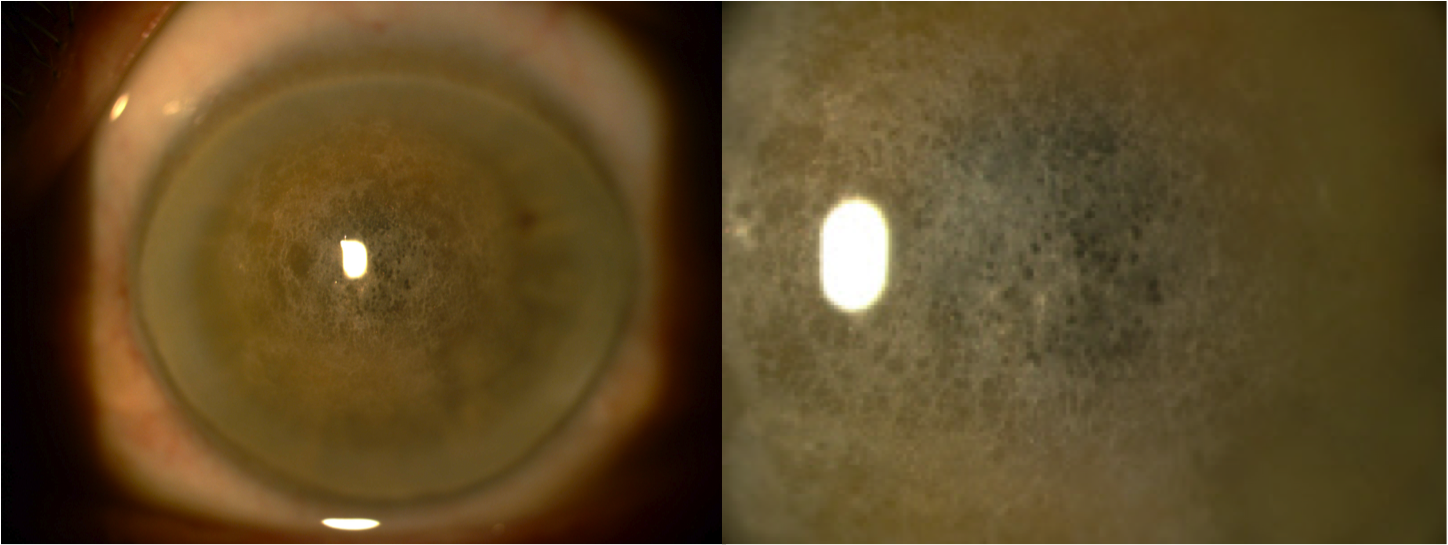

Introduction: Schnyder’s crystalline corneal dystrophy (SCCD) is a rare autossomal dominant condition characterized by abnormally increased deposition of cholesterol and phospholipids in the cornea leading to glare and disproportionate loss of photopic vision.

Results: The first case is a 60-year-old man with progressive, bilateral and painless loss of visual acuity over more than 30 years. He was clinically diagnosed with SCCD and confirmed histologically after penetrating keratoplasty. The second patient is a 41-year-old woman, daughter of the first patient, with a milder form of the disease, often more difficult to diagnose.

Conclusions: The two cases reported confirm the fact that the more elderly patients with SCCD present with increasing opacification and therefore poorer vision. The more severe form of the disease of the first patient associated with the presence of crystals makes the clinical diagnosis easier. However, the second patient could have been easily misdiagnosed. This confirms the importance of other family members examination.